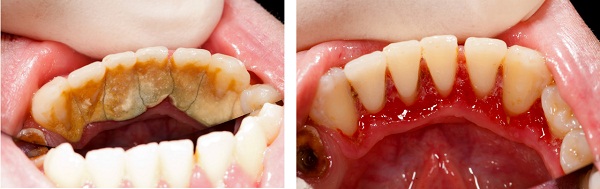

牙結石的嚴重程度如何分級?牙結石是口腔健康的重要指標,根據其覆蓋面積和位置,通常分為三個等級:

一級牙結石:牙結石覆蓋面積小於牙面的1/3,主要分布在牙齦邊緣,質地較軟,可通過規范刷牙控制發展。

二級牙結石:覆蓋面積達牙面的1/3至2/3,可見明顯的黃色或褐色沉積物,部分延伸至牙齦下方。

三級牙結石:覆蓋面積超過牙面的2/3,形成大量齦下結石,常伴有牙齦紅腫、出血等牙周症狀。

及時清除牙結石是預防牙周疾病的關鍵步驟。超聲波潔牙是目前常見清除方式,能夠去除各等級牙結石。